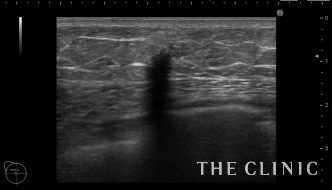

2年前に他院で脂肪注入をされた方です。

大きなしこりはありませんが、エコーでは多数のオイルシストと石灰化を認めました。

これは壊死した脂肪による石灰化です。マンモグラフィーでは粗大な石灰化で良性と診断されます。

このしこりは石灰化の近くにオイルシストを認めます。